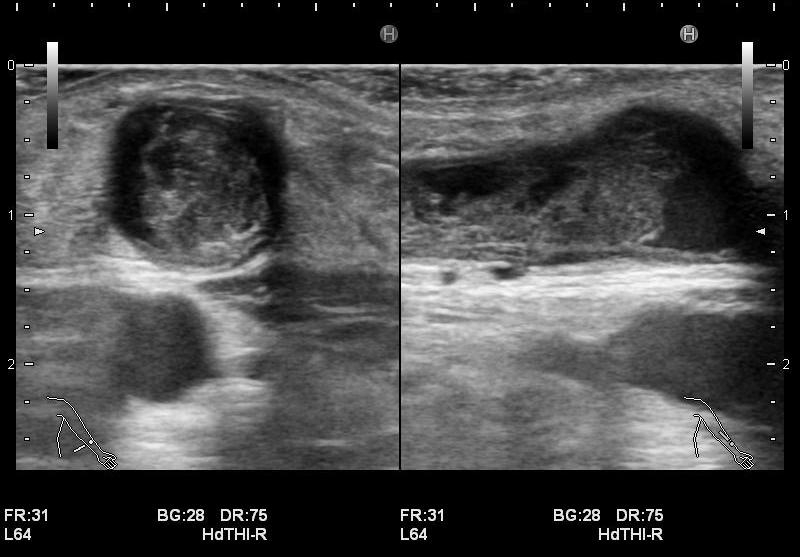

・静脈系の観察

吻合部から中枢へ向かって走査し、血管の走行や太さ、血管までの深さ、狭窄や石灰化、血栓等の有無を観察しています。長軸断面、短軸断面それぞれで観察し、また、カラードプラも使用しできるだけ正確に、血管内の状況を把握するようにしています。